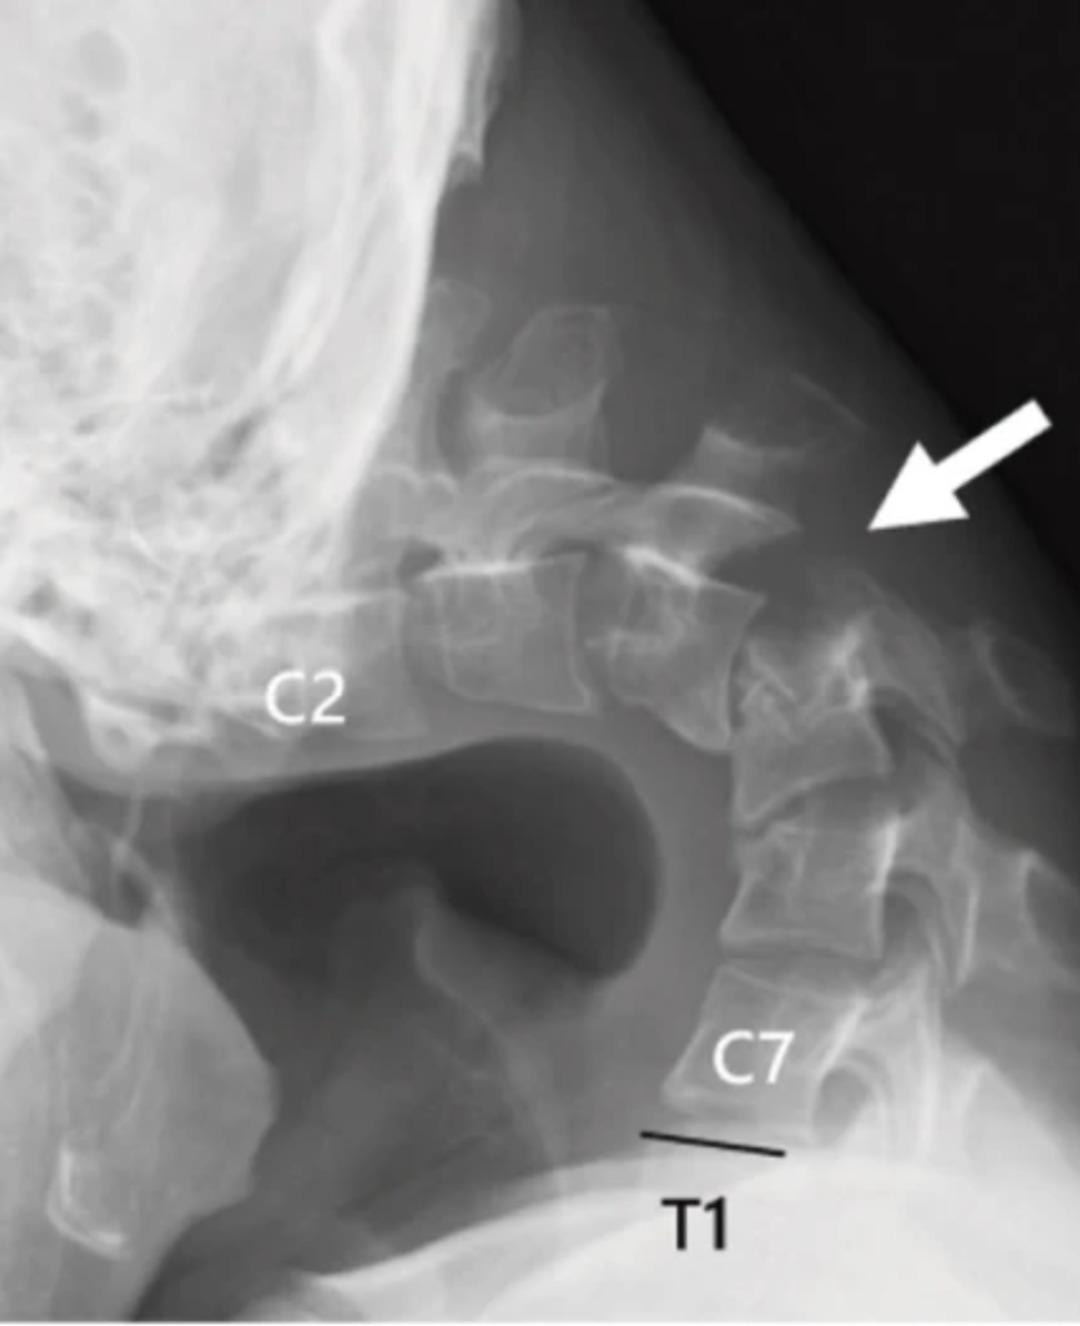

Sürekli öne eğik duruş, genç adamın boynunda bir yumru oluşmasına ve çenesinin göğsüne değecek kadar yamulmasına neden oldu. 2023’te “dayanılamaz boyun ağrısı” ve yutkunma güçlüğü çeken hasta, hızlı bir kilo kaybı da yaşadı.

Yapılan tetkiklerde omurgasında ciddi hasar ve deformasyon tespit edilirken, boyun kaslarının işlevini yitirdiği belirlendi. Doktorlar, elle müdahale ve atel kullanımının yetersiz kalması üzerine cerrahi operasyona karar verdi.

Operasyonda hasarlı omurlar ve dokular çıkarılıp, boynu hizalamak için vida ve metal çubuklar yerleştirildi. Ameliyattan altı ay sonra hasta başını kaldırmaya başladı, bir yıl içinde ise hareket kabiliyeti ve duruşunda belirgin iyileşme gözlendi. Doktorlar, genç yaşta ortaya çıkan bu vakanın nadir olduğunu belirtirken, “Düşük Kafa Sendromu”nun akıllı telefon ve tablet kullanımına bağlı olduğunu vurguladı.